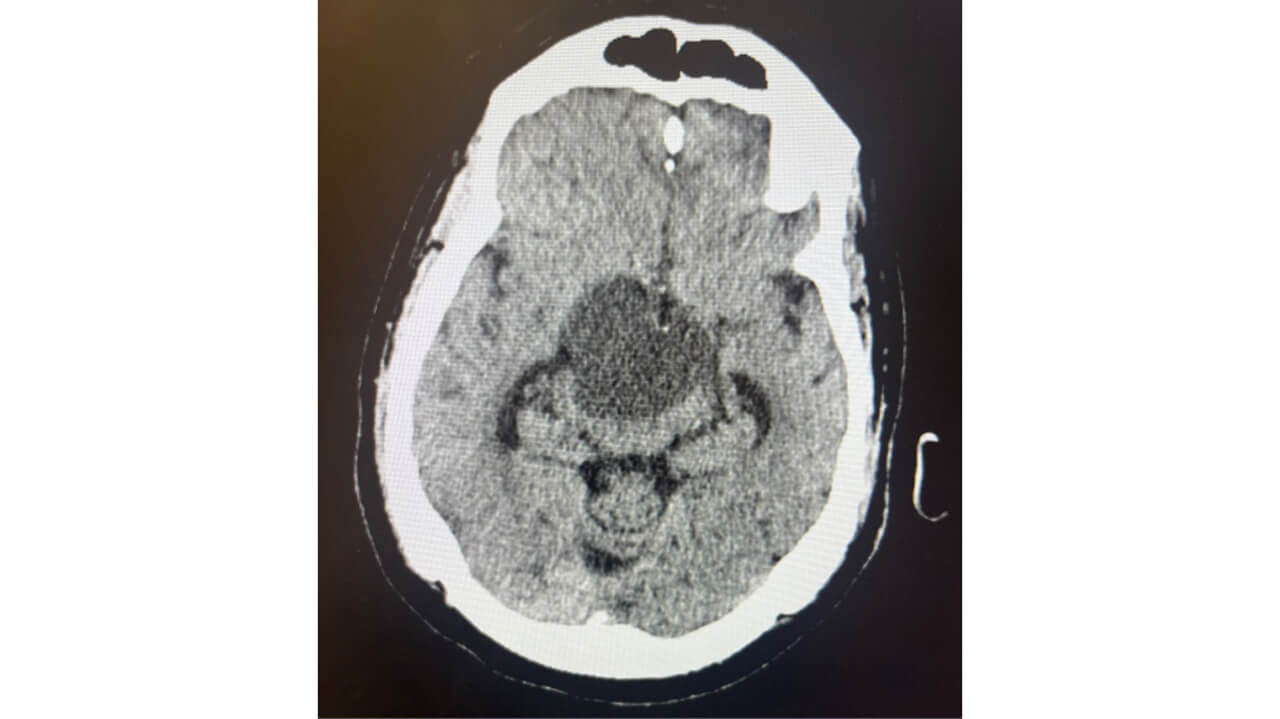

CT head w/o contrast 10/13 11am

Image 1: Craniopharyngioma